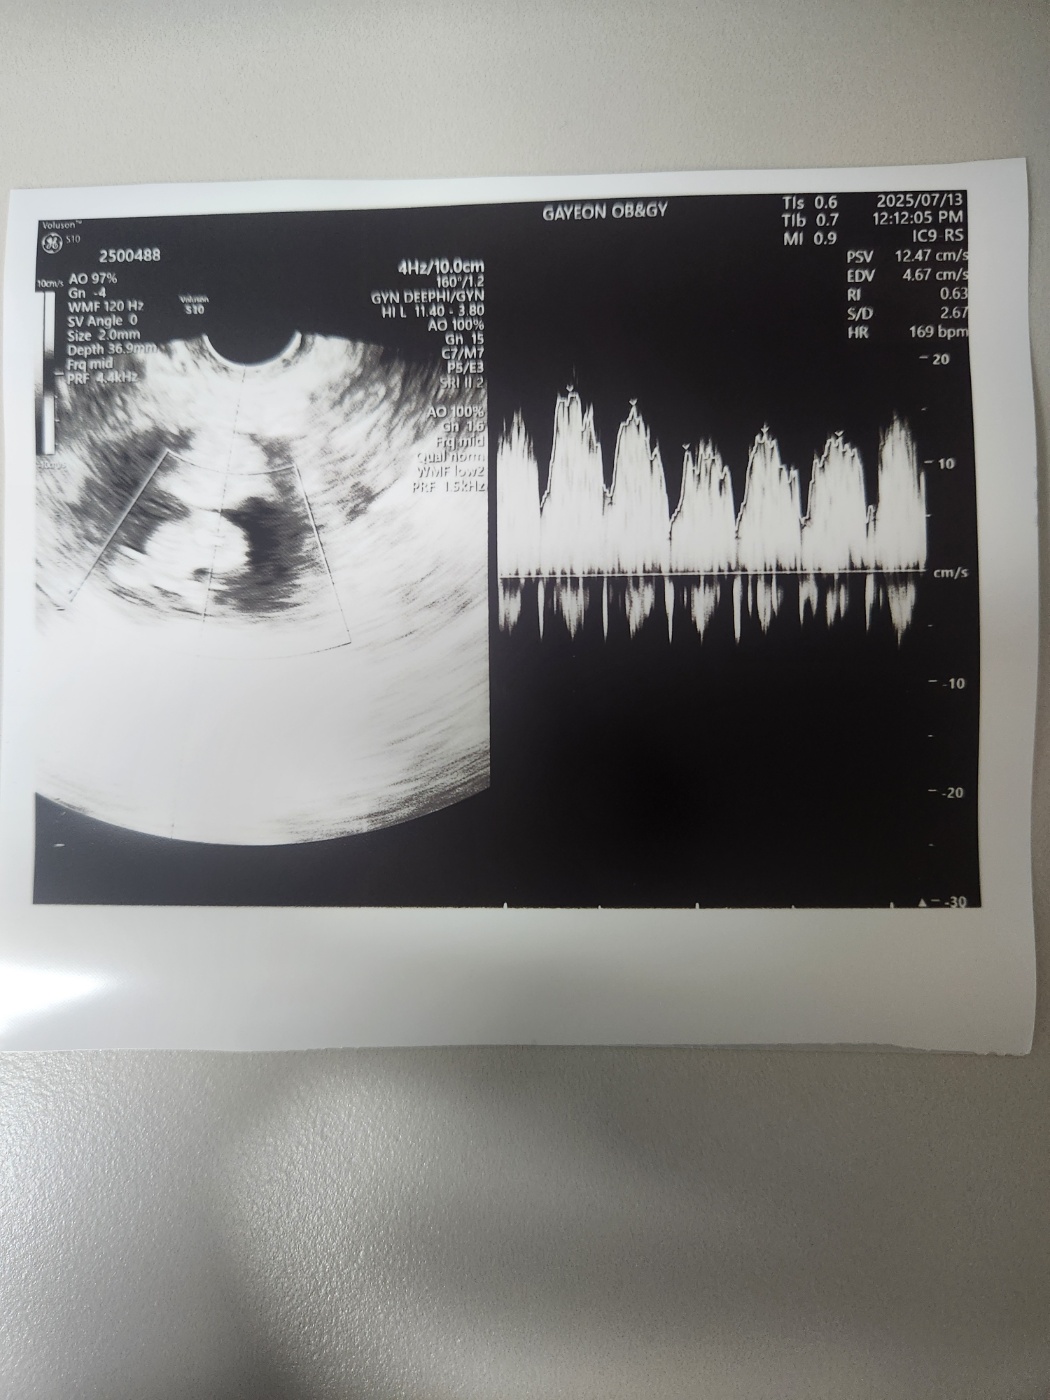

임신 9주 차의 아기 심장소리는 더욱 잘 들렸고 힘차게 뛰고 있었습니다.

의사 선생님께서는 건강하게 주수에 맞게 아주 잘 크고 있다고 말씀해 주셨습니다.